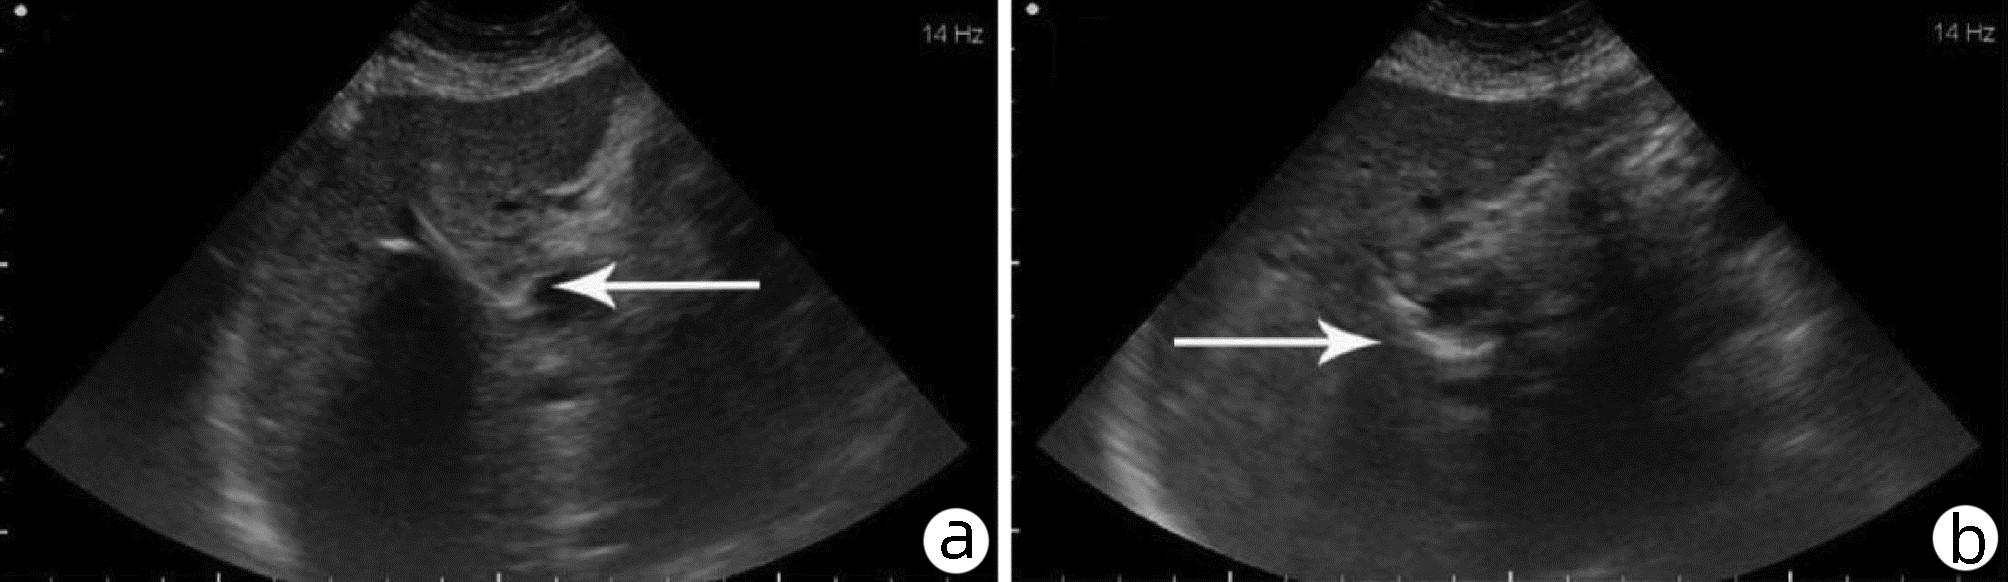

Application and clinical evaluation of ultrasound-guided biliary drainage tube replacement technology

Abstract(1345) HTML (380) PDF (1987KB)(53)

Abstract:

Objective  To summarize the preliminary application results of ultrasound-guided biliary drainage tube replacement, present the corresponding technical points, and discuss the operation strategy and clinical application value.  Methods  The clinical data of 60 patients who underwent ultrasound-guided biliary drainage tube replacement in Qilu Hospital of Shandong University between August 2014 and August 2020 were retrospectively analyzed. The operation procedure, clinical applications, and postoperative complications were summarized and analyzed.  Results  Fifty-eight of the 60 patients (96.67%) were successfully replaced with drainage tubes along the original sinus. Among them, dilated sinus tracts of 47 patients were placed with coarse-grade drainage tubes, and dilated sinus tracts of the remaining 11 patients were placed with the original type of drainage tubes, with the mean operation time of 15.8(12.0-19.0) min under local anesthesia. In total, bile was drained from 28 patients receiving PTCD drainage, 23 patients receiving gallbladder drainage, and 9 patients receiving T-tube drainage. The post-operation evaluation revealed that the drainage situation has improved, with a 100% effective rate. No obvious abnormality was found in the postoperative follow-up visit.  Conclusion  The replacement of drainage tube under ultrasound guidance is simple, safe and feasible, and it provides further promotion in clinical practice with sufficient data support.